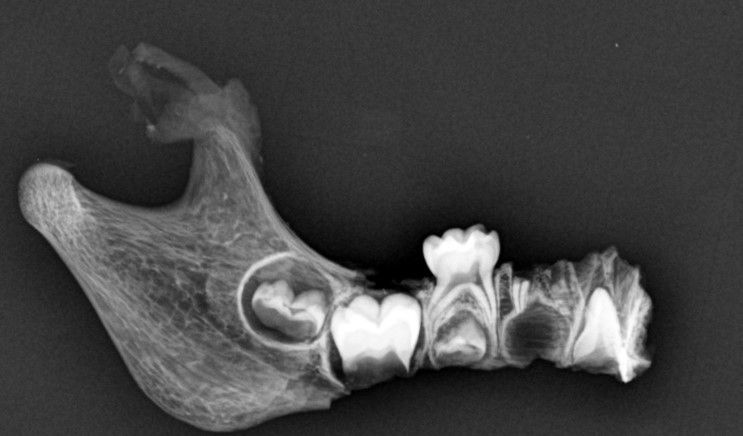

De acordo com os odontolegistas, os dois corpos carbonizados tiveram seus arcos dentários cuidadosamente examinados e radiografados. Desde ontem, a equipe do setor de Odontologia Forense vinha trabalhando, realizando várias análises para garantir uma resposta oficial para os familiares das vítimas.

A identificação da vítima foi possível através da comparação odontolegal entre os trabalhos odontológicos verificados no exame dos arcos dentários do corpo carbonizado e nas radiografias post mortem obtidas deste mesmo corpo no scanner de cadáveres com os dados fornecidos pelo cirurgião-dentista.

A Identificação de Maria de Lourdes foi possível através da comparação odontolegal entre os trabalhos odontológicos verificados no exame dos arcos dentários do corpo carbonizado e nas radiografias post mortem obtidas deste mesmo corpo no scanner de cadáveres com os dados fornecidos pelo cirurgião-dentista.

Já a segunda vítima, o menor Rafael Nilo dos Santos Nunes, foi identificada através de um trabalho minucioso de estimativa de idade realizado também com o auxílio de radiografias post mortem. Com a conclusão dos exames foi possível emitir as declarações de óbito com a identificação oficial das vítimas.